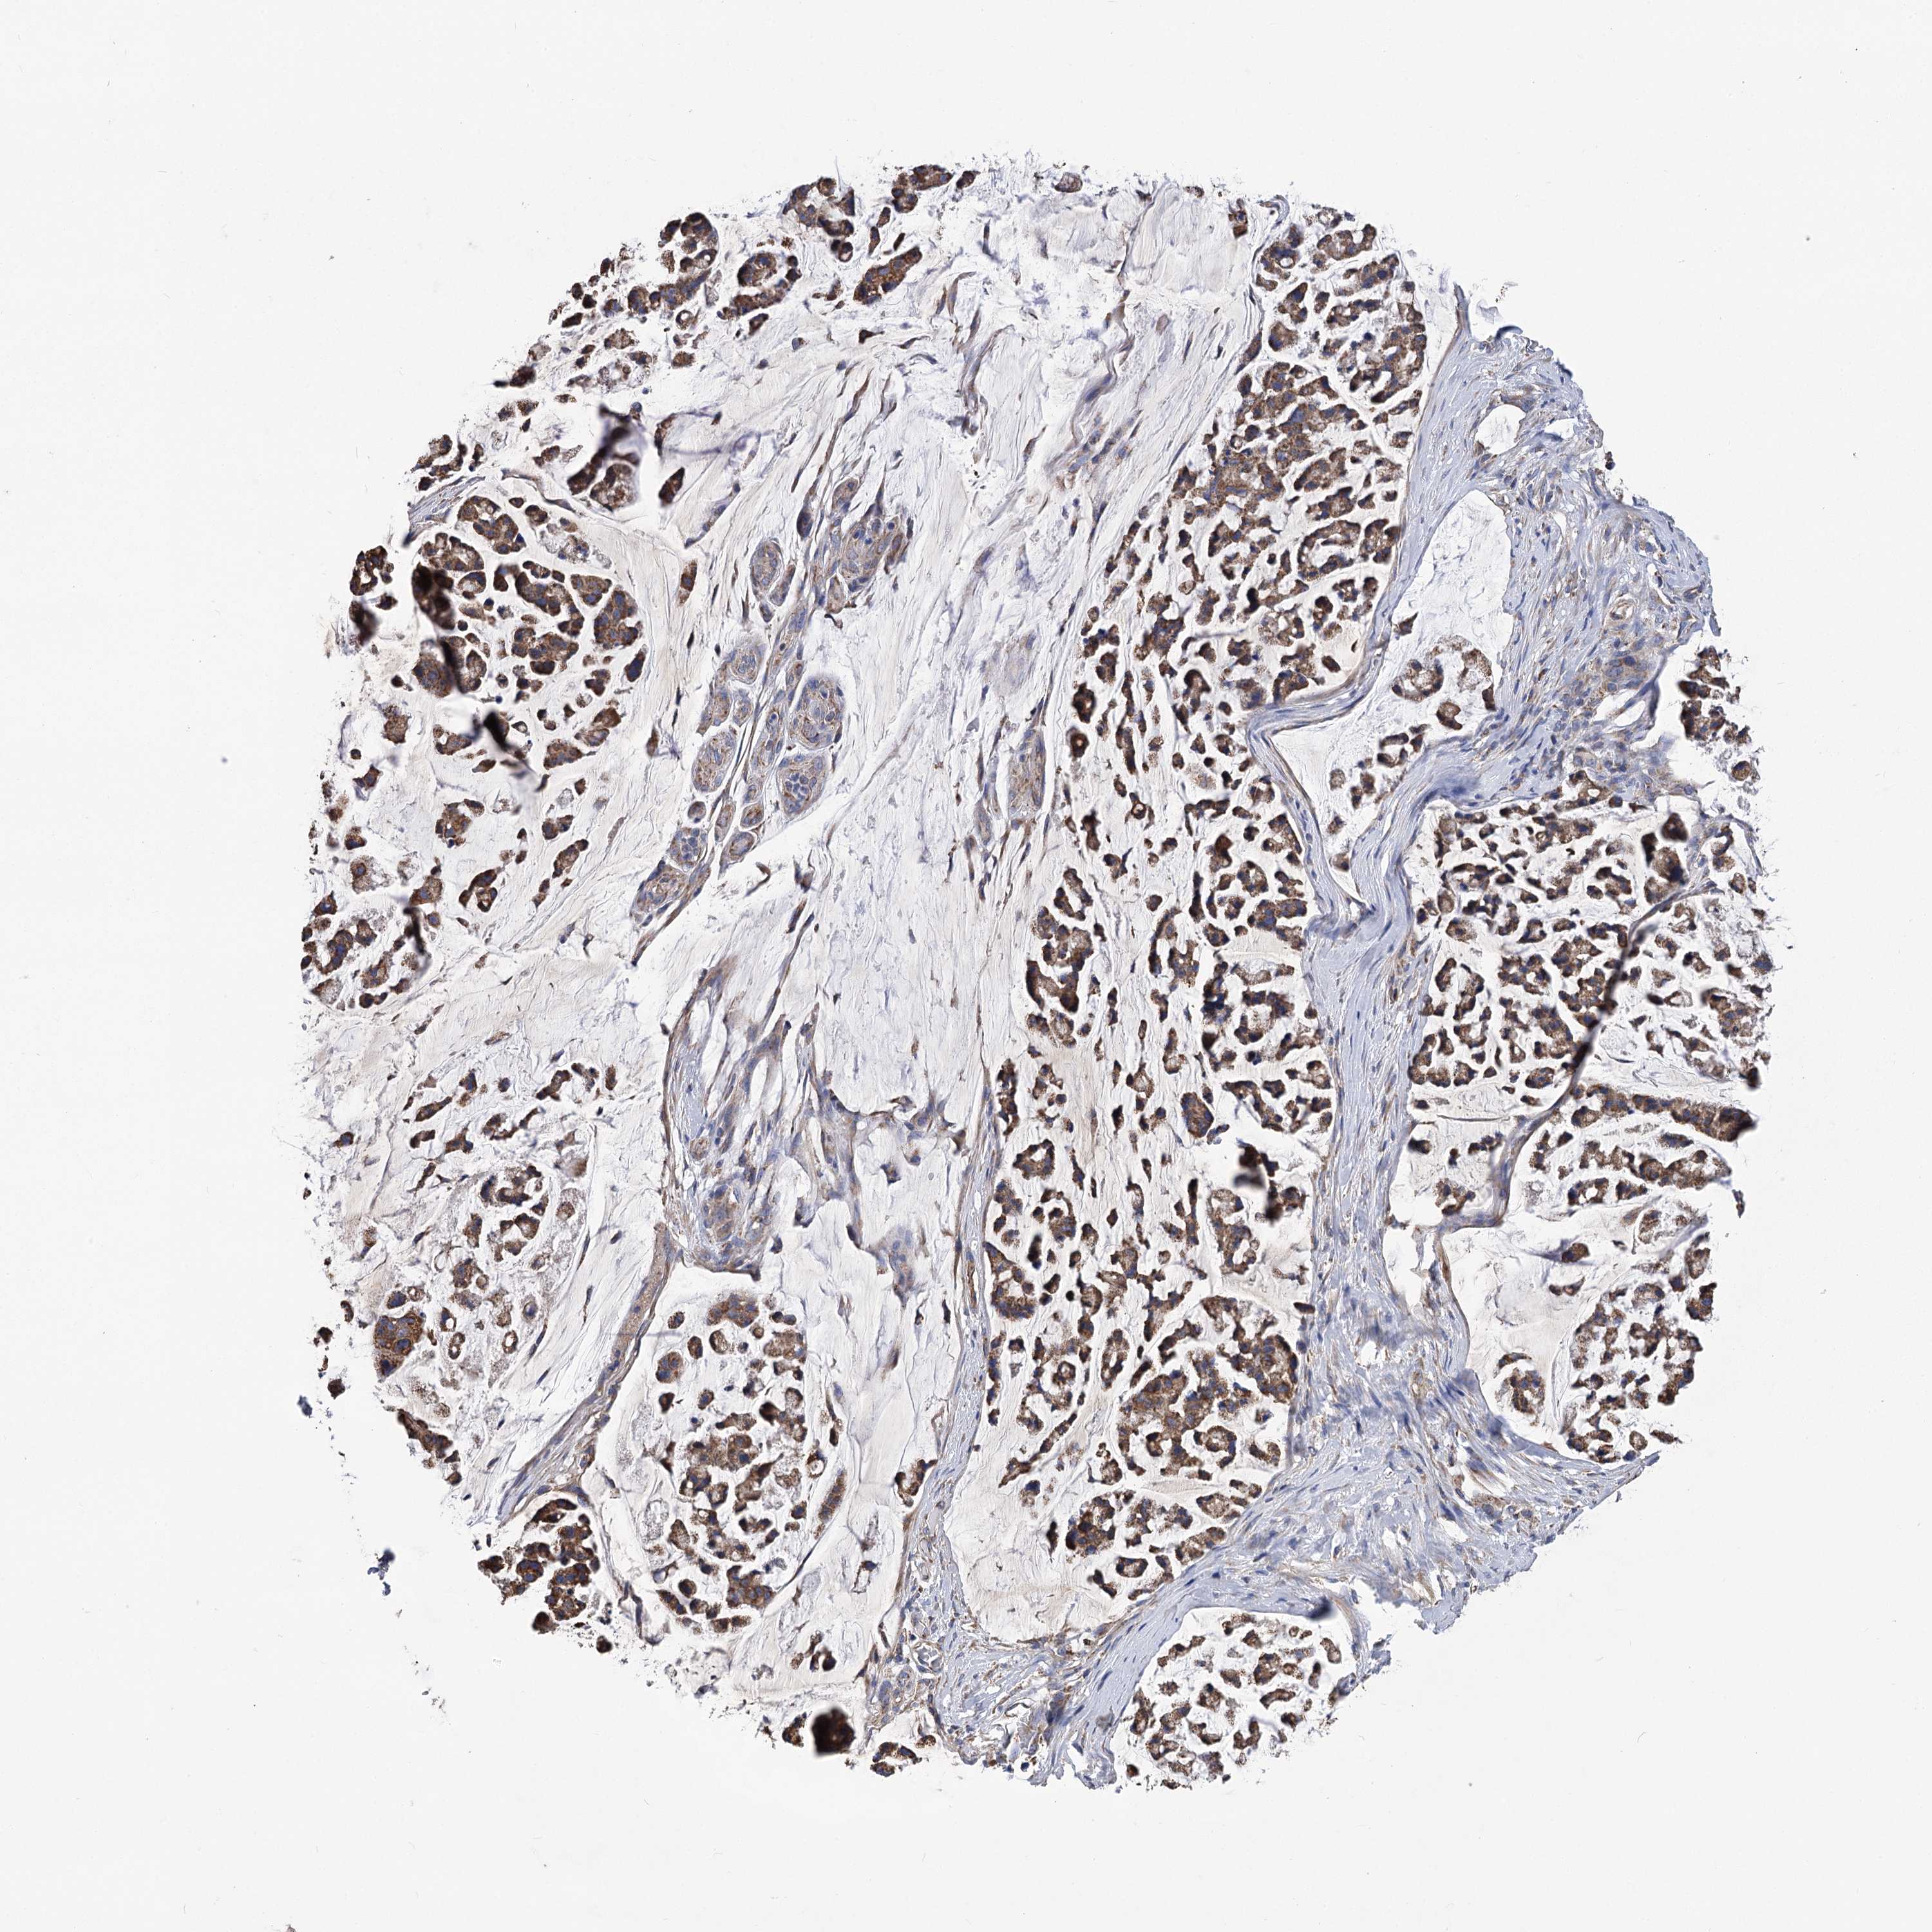

STOMACH CANCER - Protein expressioni

A mouse-over function shows sample information and annotation data. Click on an image to view it in a full screen mode. Samples can be filtered based on level of antibody staining by selecting one or several of the following categories: high, medium, low and not detected. The assay and annotation is described here.

Note that samples used for immunohistochemistry by the Human Protein Atlas do not correspond to samples in the TCGA dataset.

Antibody stainingi

Antibody staining in the annotated cell types in the current human tissue is reported as not detected, low, medium, or high, based on conventional immunohistochemistry profiling in selected tissues. This score is based on the combination of the staining intensity and fraction of stained cells.

Each image is clickable and will lead to virtual microscopy that enables deeper exploration of all samples and also displays staining intensity scores, fraction scores and subcellular localization as well as patient and tissue information for each sample.

Antibody HPA038668

Antibody HPA038669

Staining

High

Medium

Low

Not detected

Intensity

Strong

Moderate

Weak

Negative

Quantity

>75%

75%-25%

<25%

None

Location

Nuclear

Cytoplasmic/membranous

Cytoplasmic/membranous,nuclear

Adenocarcinoma, NOS

Adenocarcinoma, High grade